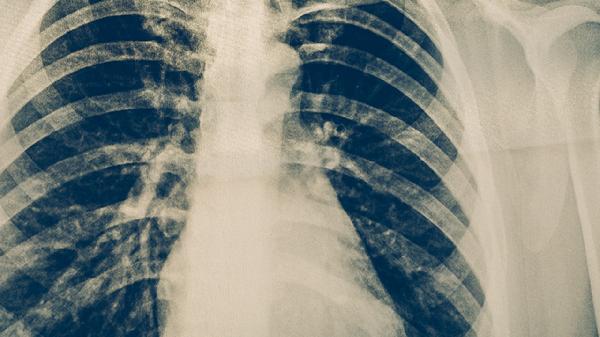

发病初期主要表现为阵发性刺激性干咳,夜间加重,多无痰或少量白色黏痰。约60%患者伴随37.5-38.5℃低热,儿童可能出现喘息症状。此阶段胸片可能显示单侧斑片状浸润影,血常规白细胞计数通常正常。

特征性表现为持续性干咳,严重时引发胸痛和呼吸困难。约20%患者发展成支气管肺炎,出现呼吸频率增快和血氧饱和度下降。肺部CT可见磨玻璃样改变,部分病例合并胸腔积液。